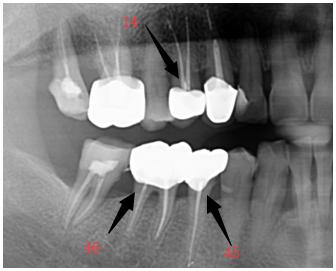

原来说起这拔牙,吴叔叔的牙齿也是“带伤上岗”多年了,三年前做过根管治疗,但是没有安装牙冠。

在这种情况下使用一直相安无事,结果几天前,那颗做了根管治疗的大牙在吃东西时崩掉出一大块,而且是钻心的疼。

根管治疗失败最为常见的就是根管的密封出现溃漏,从而导致细菌感染扩散至牙根尖,患者最明显的症状就是患牙有明显自发痛、肿胀、咬合痛等,并且长期不能缓解。